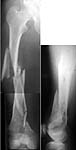

See attached case that was done several years ago before LISS. He had comminuted trochlea and anterior blocking screws were used to prevent anterior IMN cut-out.

WO> See attached case that was done several years ago

THX for the case. Very impressive. Was so fine reduction made by closed way?